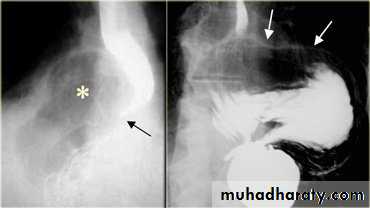

On the far left a traction diverticulum (arrow) due to hilar granulomatous disease. Calcified adenopathy (asterisk). In the middle a pulsion diverticulum (arrow) due to high intra luminal pressure.On the right multiple pulsion diverticula (arrows)

Sliding herniaOn the left initially, GE junction is below the esophageal hiatus. Later, stomach protrudes through hiatus

On the far left gas filled gastric funds (asterisk) protrudes through hiatus but GE junction (arrow) is below diaphragmThin mucosal fold (membrane)